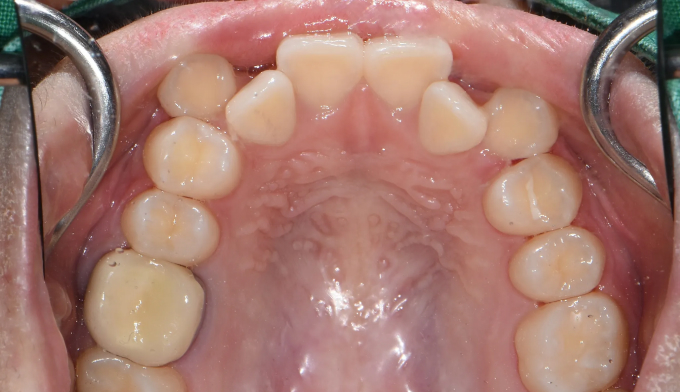

덧니가 심한 케이스 입니다. 발치를 하지 않고는 도저히 공간을 마련하기 힘들어 보입니다.

하지만 환자분의 입술이 얇고 입이 들어간 안모를 가지고 있어 섣불리 발치교정을 진행하였다가는 어색한 옆얼굴을 가지게 될 가능성이 높아집니다. 입술이 더 얇아지면서 더 나이들어보일 가능성도 높아집니다.

최대한 좁은 악궁을 확장하고 부족하면 전체 치열의 후방이동을 통하여 덧니를 배열할 공간을 만들었습니다.